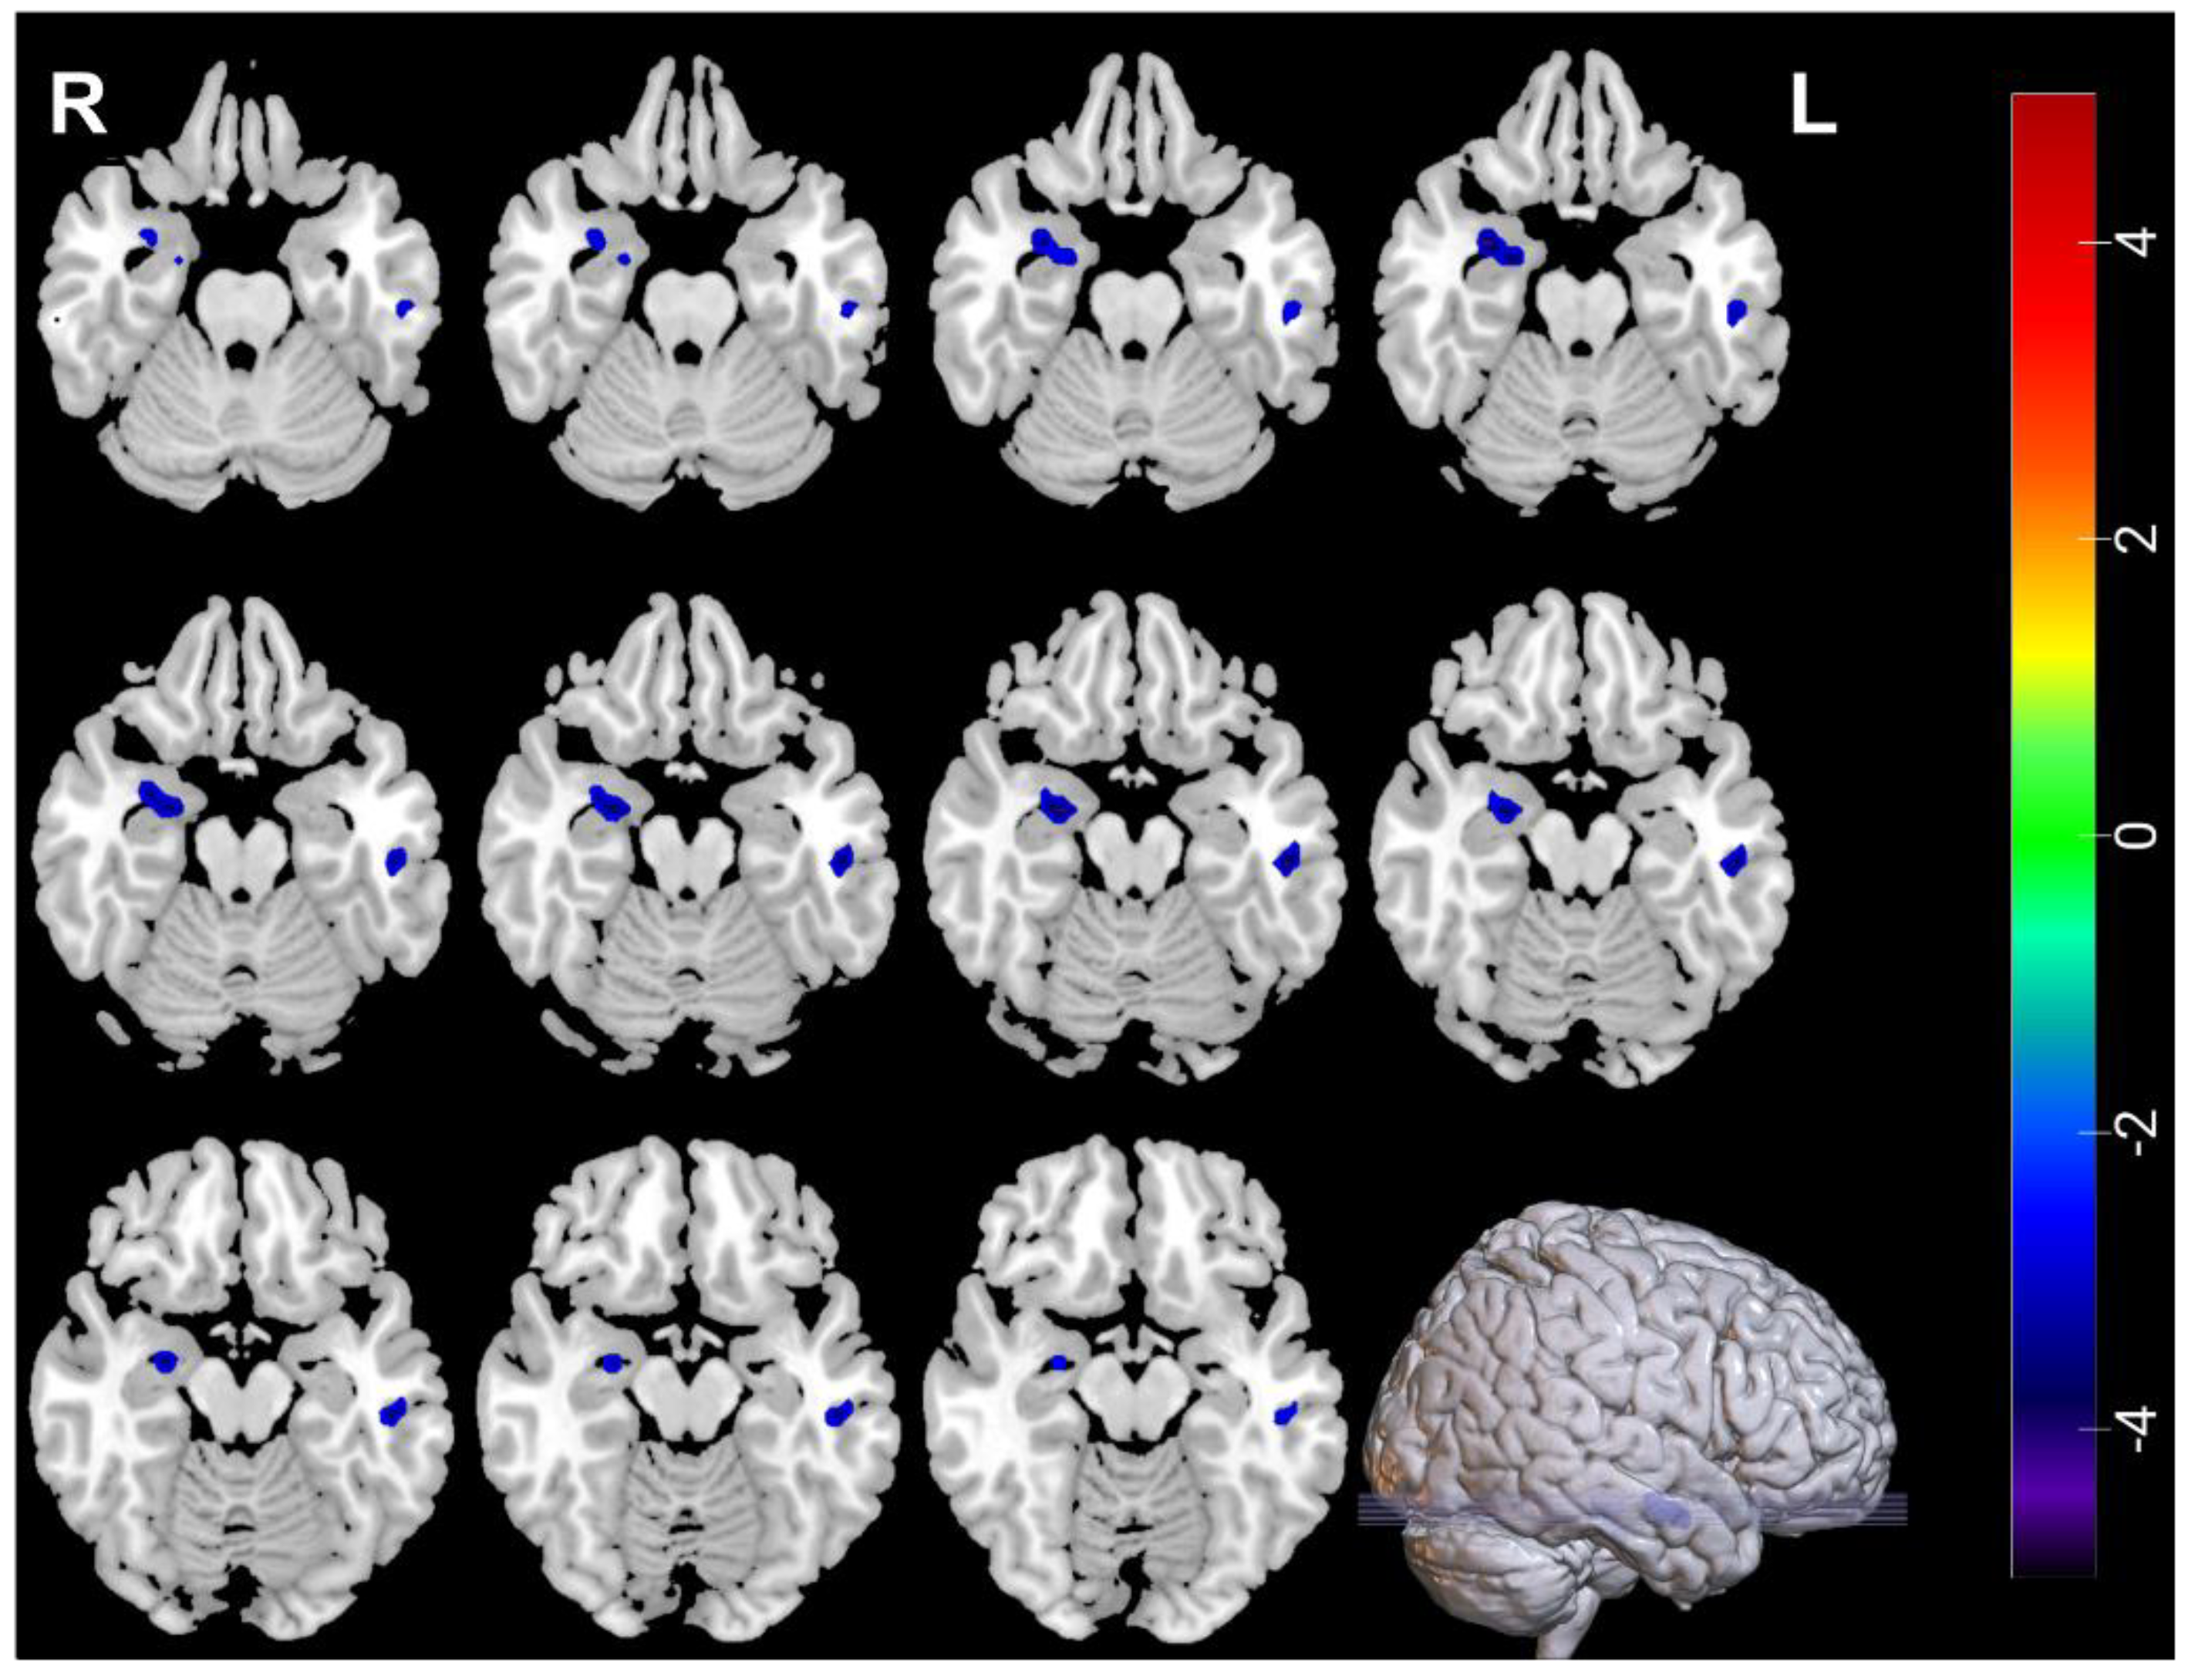

3.2. Neuroimaging Comparisons between MDDs at Baseline and HCs

| Measures | Brain Regions | Voxel Size | Peak t Value | MNI Coordinates | ||

|---|---|---|---|---|---|---|

| Decreased | ||||||

| ALFF | Amygdala_R | 31 | −4.637 | 33 | 0 | −21 |

| ALFF | Temporal_Inf_L | 30 | −3.6166 | −51 | −24 | −18 |

| ReHo | Temporal_Inf_L | 45 | −4.3107 | −48 | −21 | −18 |

| Increased | ||||||

| ReHo | Frontal_Inf_Oper_R | 40 | 4.0503 | 63 | 15 | 15 |

| ReHo | Occipital_Mid_L | 41 | 3.7464 | −36 | −84 | 6 |